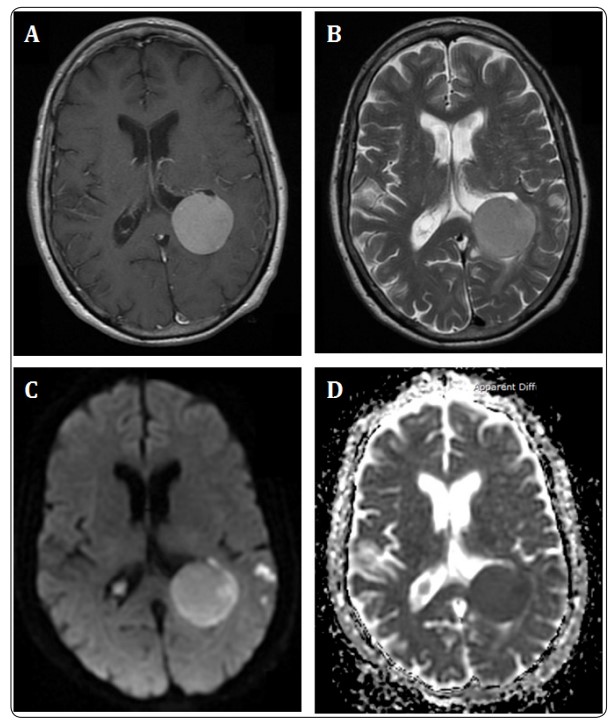

GBCAs are types of contrast agents given intravenously, through a small needle into a vein in the arm, and are used for imaging procedures during MRI scans3. They are administered to provide sharper MRI images and have been used to aid imaging of tumors, blood vessels, and inflammation3. While GBCAs are still available for administration, the Food and Drug Administration (FDA) has now issued a warning on the use of GBCAs due to concerns over how long they stay in the body, especially in people with kidney problems4. GBCAs can be characterized as macrocyclic or linear, with macrocyclic GBCAs generally being more stable, and linear GBCAs having more of a risk of remaining in the body. Generic types of GBCAs include gadopentetate dimeglumine (linear) and gadoterate meglumine (cyclic)4.

A safe alternative to gadolinium contrast includes non-contrast MRI scans, especially for individuals with increased risk of having adverse effects after receiving GBCAs, including those with kidney problems, pregnant individuals, and those with allergies to contrast dyes. When contrast is necessary, for example, for those having an MRI scan for brain lesions, there should be discussions with healthcare providers to assess alternative imaging options like iodinated contrast or low-dose radiation computed tomography (CT) scans. Iodine is highly effective for enhancing CT and X-ray scans and can be used for a wide range of body areas and procedures14. Here at Ezra, we offer non-invasive, fast, contrast-free MRI scans, which are safe and still highly effective. We also offer low-dose radiation CT scans, which use a similar technology to regular CT scans but emit much less ionizing radiation for screening of the lungs.

Due to its ability to sharpen MRI scan images, making abnormal tissues, blood vessels, inflammation, tumors, and blood clots more visible and easier to diagnose3.